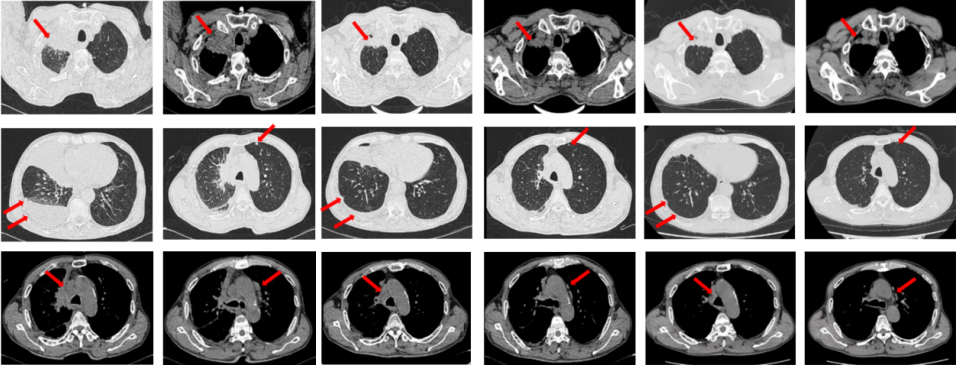

2022年7月至2022年11月行贝伐珠单抗联合培美曲塞/顺铂方案治疗6周期,2周期后评效PR,4周期后评效SD-(如图1)。第6周期治疗结束后患者自行终止治疗。

图1:由左至右分别展示基线(A.)及一线治疗后改变(B.和C.)。红色箭头指示病灶位置,由上至下分别为右肺肿物、右侧胸膜转移病灶及胸腔积液、左侧胸膜转移病灶、多发纵隔淋巴结肿大。

2023年3月患者因咳嗽伴胸闷复查出现全面PD。2023年3月-2023年4月重启原方案贝伐珠单抗联合培美曲塞/顺铂治疗2周期。2023年5月复查评效PD。行左锁骨上淋巴结穿刺,病理回报:左锁骨上见异型细胞,考虑为癌可能性大。组织NGS基因检测:MET基因扩增(变异倍数)2.0倍,TP53错义突变,PD-L1(22C3):TPS 75%。2023年5月-2023年8月改行替雷利珠单抗联合紫杉醇脂质体治疗4周期,2周期后评效SD。(如图2)

图2:A.代表一线治疗停药后病情进展,右肺上叶肿物、右侧胸膜转移灶及纵隔淋巴结较前增大、增多,右侧胸腔积液较前增多;B.原方案重启后复查评效右肺上叶肿物及纵隔淋巴结较前略饱满,右侧胸腔积液较前明显增多;C.更改二线治疗方案后整体病灶较前无显著变化。

2023年9月复查评效PD。成功入组“一项开放、多中心对比谷美替尼与多西他赛在既往接受免疫治疗和含铂双药化疗后进展的驱动基因阴性且伴有MET扩增的局部晚期或转移性非小细胞肺癌患者中的随机对照III期临床研究”。成功随机到试验组,口服谷美替尼至2024年10月,期间复查最佳评效PR。

图3:A.二线治疗后病情进展,右肺上叶新发肿物较前明显增大,新发无症状脑转移病灶;B.经谷美替尼(300mg po qd)治疗3个月后复查肺内病灶及颅内病灶较前明显缓解